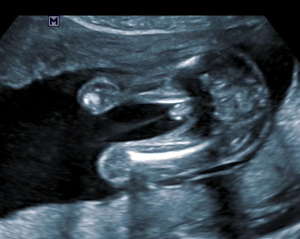

20 weken echo (ETSEO)

Deze echo wordt ook wel structureel echoscopisch onderzoek genoemd (SEO) en valt onder prenatale screening. Indien je deze echo wenst wordt deze rond de 20 weken zwangerschap verricht. Het betreft een echo waarbij het kindje wordt gescreend op lichamelijke afwijkingen.